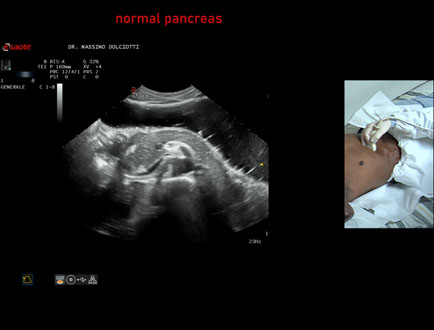

Data inserimento: 21/01/2026

Ecografia del: 14/01/2026

Strumento: Esaote MyLab Eight

Sonda: Convex Multifrequenza 1-8 MHz

Età Paziente: M 29 anni

Motivazione dell'esame: epatopatia virale

Commento all'esame: le immagini ed il video documentano il pancreas ipoecogena, di ecostruttura e morfovolumetria regolare, esaminato in posizione supino e laterale destra.

Conclusioni: pancreas normale (normal pancreas).

In collaborazione: Dr.ssa Marica Manfredi - Ancona, Dr. Ilir Qose - Ancona

Presentazione: Dr. Massimo Dolciotti - Ancona